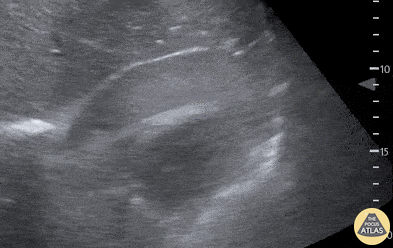

Pericardial Disease - Traumatic Tamponade

27-year-old woman presents with gunshot wound to right chest. Patient phonating on arrival but tachycardic in 150s with BP 60/palp. EFAST revealed pericardial effusion with hematoma and near complete RV diastolic collapse, consistent with cardiac tamponade. Decision was made to take patient directly for OR thoracotomy based on EFAST findings. Patient lost pulses for 10 sec intra-operatively prior to receiving pericardial window. ROSC was achieved with removal of pericardial hematoma. LV laceration was identified and repaired. LAD laceration identified for which patient received emergent CABG by CT surgery. Patient was successfully extubated the next day, discharged one week later. EFAST aids in rapid diagnosis and expedites care in hemodynamically unstable trauma patients. POCUS is a useful tool for determining etiology of undifferentiated shock. Quinn Fujii DO, William Hamrick DO, Ulysses Garcia DO, Robert Rigby DO Desert Regional Medical Center, Emergency Medicine